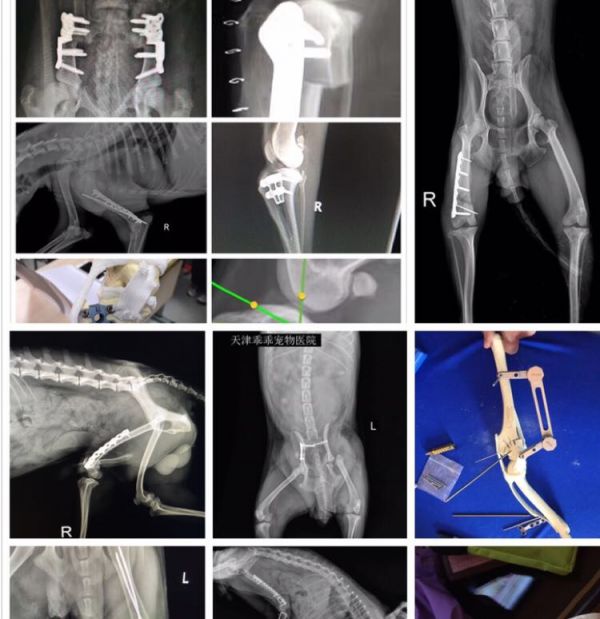

职业兽医师 天津熊猫宠物医院创始人院长 兽医协会宠物诊疗分会理事 兽医外科学会会员 吉林农业科技学院特聘讲师~中国百佳宠物医师